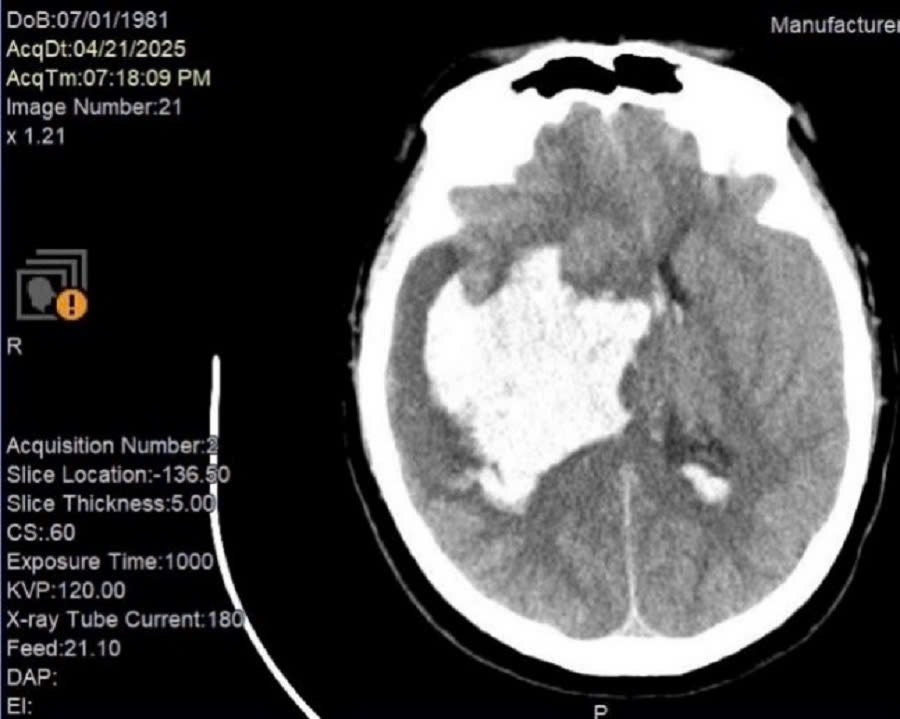

Một trường hợp bệnh nhân nam T. 44 tuổi bị đột quỵ xuất huyết não nặng nguyên nhân do tăng huyết áp. Ca xuất huyết não này không thể làm gì cả. Mơ ước của người nhà là bác sĩ cố gắng hết sức… gia đình có điều kiện nên cần làm gì cứ làm! Các bác sĩ chỉ biết ngậm ngùi… giá như bệnh nhân đến trong ngày hôm qua lúc nguy cơ đột quỵ (tăng huyết áp) chưa trở thành thảm họa. Để hôm nay hai chữ “giá như” bác sĩ không thể nói lúc bệnh nhân đang hấp hối. Vì cho dù đúng nhưng sẽ tàn nhẫn với người ở lại biết bao nhiêu.